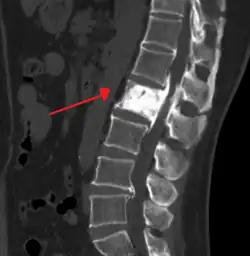

Initially, there is a marked increase in the rate of bone resorption in localized areas, caused by large and numerous osteoclasts. Radiographs at this phase show lucency in the affected bone. These localized areas of pathological destruction of bone tissue (osteolysis) are seen radiologically as an advancing lytic wedge in long bones or the skull. When this occurs in the skull, it is called osteoporosis circumscripta. The osteolysis is followed by a compensatory increase in bone formation and increase in alkaline phosphatase levels induced by the bone-forming cells, called osteoblasts, that are recruited to the area. This is associated with accelerated deposition of lamellar bone in a disorganized fashion. Woven bone, rather than lamellar bone, predominates and mineralization occurs at twice the normal rate.[5] This intense cellular activity produces a chaotic picture of trabecular bone ("mosaic" pattern), rather than the normal linear lamellar pattern. The resorbed bone is replaced and the marrow spaces are filled by an excess of fibrous connective tissue with a marked increase in blood vessels, causing the bone to become hypervascular. The bone hypercellularity may then diminish, leaving a dense "pagetic bone", also known as burned-out Paget's disease. A later phase of the disease is characterized by the replacement of normal bone marrow with highly vascular fibrous tissue.[25]

- Pagetic bone has a characteristic appearance on X-rays. A skeletal survey is therefore indicated.